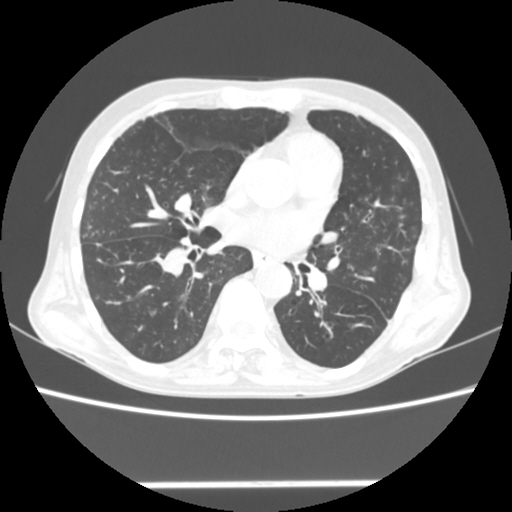

A 54 years old man with intermittent cough with expectoration and shortness of breath since childhood (Radiology)

Radiological images: